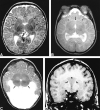

<sc>fig</sc> 1.

fig 1.

Range of noncleavage of the basal ganglia and thalamus. A, Grade 0: Axial T2-weighted image at the level of the third ventricle shows the abnormally deep anterior IHF (long arrow) and widely separated caudate and lentiform nuclei (short arrows). B, Grade 1: Axial T2-weighted image at the level of the third ventricle shows the medial location and small amount of contact between the caudate nuclei (arrow). Note also the noncleavage of the claustra (arrowheads) and probable anterior limbs of the internal capsules (white matter posterior to claustra). C, Grade 2: Axial T2-weighted image in a more severely affected patient shows the partial noncleavage of the lentiform nuclei (white arrows) and thalami (black arrows). D, Grade 3: Coronal 3D spoiled gradient-echo image through the caudate heads shows complete failure of cleavage (arrows).

<sc>fig</sc> 2.

fig 2.

Range of noncleavage of the hypothalamus. A, Grade 1: Coronal T2-weighted image shows the attenuated anterior recess of the third ventricle (arrow) in the setting of partial hypothalamic noncleavage. B, Grade 2: Coronal T1-weighted image shows the continuity of the hypothalamus across the midline of the basal forebrain (short arrow). Note the associated ectopic neurohypophysis (long arrow). fig 3. Deep gray nuclear mass. Axial T1-weighted image shows the noncleaved deep gray nuclear mass, which is diminished in volume and without discernible structures (arrows)